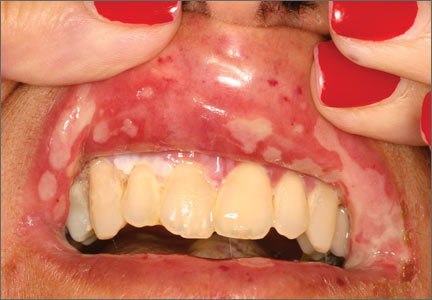

Primary herpes simplex virus 1 (HSV-1) infection is generally subclinical, but some patients develop significant oral disease—called primary herpetic gingivostomatitis—that’s characterized by painful diffuse, irregular, crop-like ulcerations throughout the oral cavity and lips1 (FIGURE 1). The gingiva is nearly universally affected, which distinguishes this condition from erythema multiforme and aphthous stomatitis, which are described below. The incidence is highest in children, followed by adolescents and young adults.2